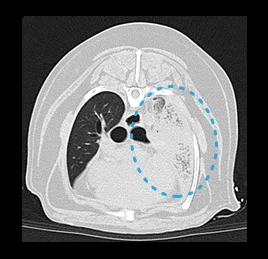

• 폐 염전

• 폐 종양